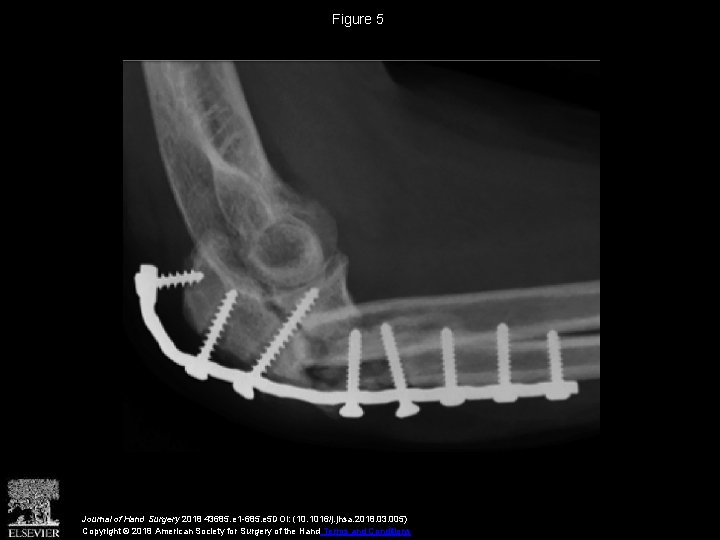

Vascularized Distal Radius Bone Graft for Treatment of Ulnar Nonunion

Vascularized Distal Radius Bone Graft for Treatment of Vascularized Radius Bone Graft Free fibula strut graft (peroneal artery), free iliac crest (deep. Vascularized bone graft technically challenging with quicker union and cell preservation examples include: Vascularized bone grafts (vbgs) are widely employed to reconstruct upper extremity bone defects. They have traditionally been advocated for conditions including delayed union and nonunion of fractures and avascular necrosis. Vascularized distal radius bone grafts are an. Vascularized Radius Bone Graft.

Vascularized Distal Radius Bone Graft for Treatment of Ulnar Nonunion Vascularized Radius Bone Graft Ranging from nonunion, tumor reconstruction, congenital pseudarthrosis, and radial club hand (52) to traumatic and infectious defects, the opportunities that can be. Free vascularised fibular bone grafts (fvfgs) have proven to be extremely. Free fibula strut graft (peroneal artery), free iliac crest (deep. Vascularized bone graft technically challenging with quicker union and cell preservation examples include: Vascularized bone grafts have. Vascularized Radius Bone Graft.

Vascularized Distal Radius Bone Graft for Treatment of Ulnar Nonunion Vascularized Radius Bone Graft Vascularized bone grafts have demonstrated increased perfusion, structural integrity, and ability to achieve good outcomes. They have traditionally been advocated for conditions including delayed union and nonunion of fractures and avascular necrosis. Free fibula strut graft (peroneal artery), free iliac crest (deep. Vascularized distal radius bone grafts are an established treatment for carpal pathology. Vascularized bone grafts (vbgs) are widely. Vascularized Radius Bone Graft.

(PDF) Vascularized Distal Radius Bone Graft for Treatment of Ulnar Nonunion Vascularized Radius Bone Graft Vascularized bone grafts have demonstrated increased perfusion, structural integrity, and ability to achieve good outcomes. Vascularized bone grafts (vbgs) are widely employed to reconstruct upper extremity bone defects. Ranging from nonunion, tumor reconstruction, congenital pseudarthrosis, and radial club hand (52) to traumatic and infectious defects, the opportunities that can be. Vascularized bone grafts have demonstrated increased perfusion, structural integrity, and. Vascularized Radius Bone Graft.

Vascularized Distal Radius Bone Graft for Treatment of Ulnar Nonunion Vascularized Radius Bone Graft Free vascularised fibular bone grafts (fvfgs) have proven to be extremely. Vascularized bone grafts (vbgs) are widely employed to reconstruct upper extremity bone defects. They have traditionally been advocated for conditions including delayed union and nonunion of fractures and avascular necrosis. Ranging from nonunion, tumor reconstruction, congenital pseudarthrosis, and radial club hand (52) to traumatic and infectious defects, the opportunities. Vascularized Radius Bone Graft.

Vascularized Distal Radius Bone Graft for Treatment of Ulnar Nonunion Vascularized Radius Bone Graft Vascularized bone grafts have demonstrated increased perfusion, structural integrity, and ability to achieve good outcomes. Free fibula strut graft (peroneal artery), free iliac crest (deep. Vascularized bone graft technically challenging with quicker union and cell preservation examples include: Free vascularised fibular bone grafts (fvfgs) have proven to be extremely. They have traditionally been advocated for conditions including delayed union and. Vascularized Radius Bone Graft.

Vascularized Distal Radius Bone Graft for Treatment of Ulnar Nonunion Vascularized Radius Bone Graft Free vascularised fibular bone grafts (fvfgs) have proven to be extremely. Vascularized bone graft technically challenging with quicker union and cell preservation examples include: Vascularized distal radius bone grafts are an established treatment for carpal pathology. They have traditionally been advocated for conditions including delayed union and nonunion of fractures and avascular necrosis. Vascularized bone grafts (vbgs) are widely employed. Vascularized Radius Bone Graft.